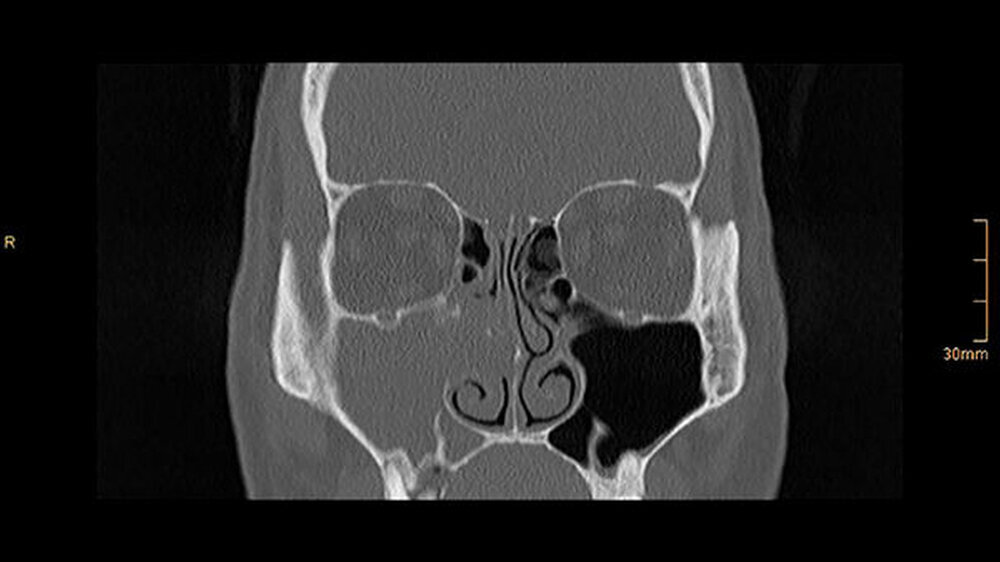

Die CT-Aufnahmen zeigen eine deutliche bis zum Orbitaboden heranreichende Totalverschattung der rechten Kieferhöhle. In Höhe des Zahns 16 zeigen sich periradikuläre Rarefikationen als Hinweis auf eine aggressive lokale Parodontitis.